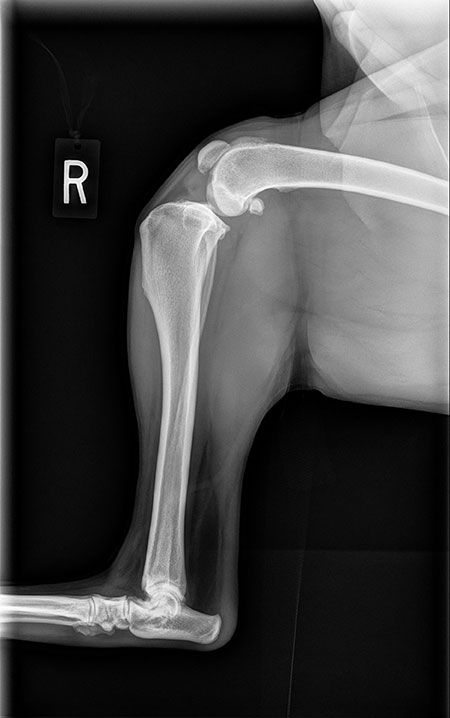

Symptoms of Cruciate Disease in dogs. This conservative approach only tends to be effective in small breed dogs. Injury or failure of the cranial cruciate ligament commonly referred to as Cruciate Disease is a very common problem that can be encountered by dogs of all shapes and sizes. You may hear the same condition referred to as anterior cruciate ligament disease CCL or ACL disease cruciate tear or rupture or injury or just cruciate diease. Sudden lameness in a rear leg is often the first sign of injury. In the stifle knee of the dog two ligaments called cruciate ligaments hold the femur thigh bone to the tibia shin bone. Cruciate ligament surgery for dogs. Facts About Cranial Cruciate Ligament Disease in Dogs It is the most common orthopedic condition in dogs out of about 40 conditions affecting back legs in dogs CCL injuries are a relatively rare orthopedic condition in cats Dogs can have a partial or complete rupture of the CCL. Cranial cruciate ligament disease CCLD is one of the most common orthopaedic conditions in dogs Johnson et al 1994.

Inside the canine knee there are two crossing ligaments that join the tibia and the femur. Some dogs with cruciate disease will have several episodes of waxing and waning lameness before the ligament finally tears completely. Generally cruciate disease is managed with surgery unless the lameness is very mild. Inside the canine knee there are two crossing ligaments that join the tibia and the femur. Sudden lameness in a rear leg is often the first sign of injury. In humans this ligament ACL can rupture for example when skiing or playing football. You may hear the same condition referred to as anterior cruciate ligament disease CCL or ACL disease cruciate tear or rupture or injury or just cruciate diease.